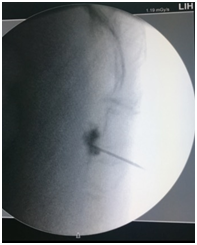

We describe the case of a 59 years old woman affected by rectal cancer which was diagnosed in April 2016 and involved the rectum from the anal margin for an extension of 7 cm and extended into the mesorectal lymphonodes withouth metastes (Figure 1). The patient underwent radiation and chemotherapy to reduce cancer mass. After 6 months, though, a full body CT scan showed a reduction of cancer mass into the rectum (which measured 2,5 cm from the anal margin with no lymphatic involvement) but multiple hepatic metastases were detected. The patient was not proposed for surgery due to the hepatic involvement and was given another chemotherapy cycle comprising cisplatin and fluorouracil. The patient complained of severe pain located in the perianal and perineal region, which was exacerbated by defecation. Basal Numerical Rating Score (NRS) for pain was 8 out of 10 and during defecation the patient reported a NRS of 10. Pharmacological treatment with dexamethasone, transdermal fentanyl and paracetamol didn’t give the patient substantial improvement. The patient was admitted to Palliative Care Department where Pregabalin was added and Fentanyl was replaced with subcutaneous Morphine 100mg/day. Even with this therapy the patient was still complaining for severe pain located in the perianal region. Rectal exploration was impossible for the extreme pain elicited in the patient by this manouver. After a consultation with the patient’s caregiver and the palliative care staff we decided to propose the patient for ganglion impar Radiofrequency (RF) ablation. Written consent was obtained from the patient. The procedure was performed under sterile conditions with fluoroscopic guidance. Antibiotic prophylaxis with intravenous cefazolin 2 g was given. The patient was prone positioned with a pillow under the iliac crests to reduce lumbar lordosis. Skin was anesthetized with 2% Lidocaine and a 18G 100 mm long RF needle with an active tip of 5 mm was inserted under fluoroscopic lateral vision at the sacro-coccygeal junction and the needle tip was positioned under the sacro-coccygeal ligament. Contrast (iopamidol 300) was injected and no vascular or epidural absorption was noticed, the contrast spread between the coccyx and the rectum outlining the ganglion impar (Figure 2) Sensory stimulation at 50 Hz was performed and the patient reported paraesthesia in the perianal region at 0.4 A intensity.

Figure 1 CT Scan showing rectal cancer.